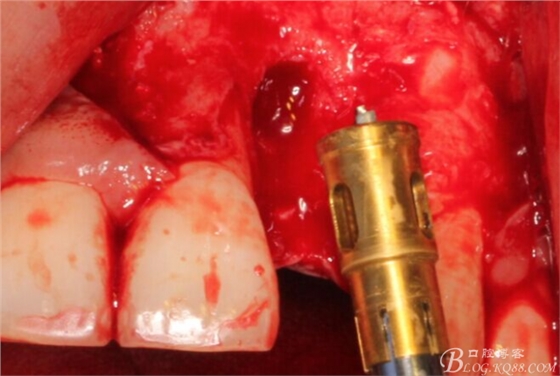

徹底搔刮拔牙窩,偏腭側(cè)備洞

順利植入植體,扭力30N。三壁骨,感覺美美的。